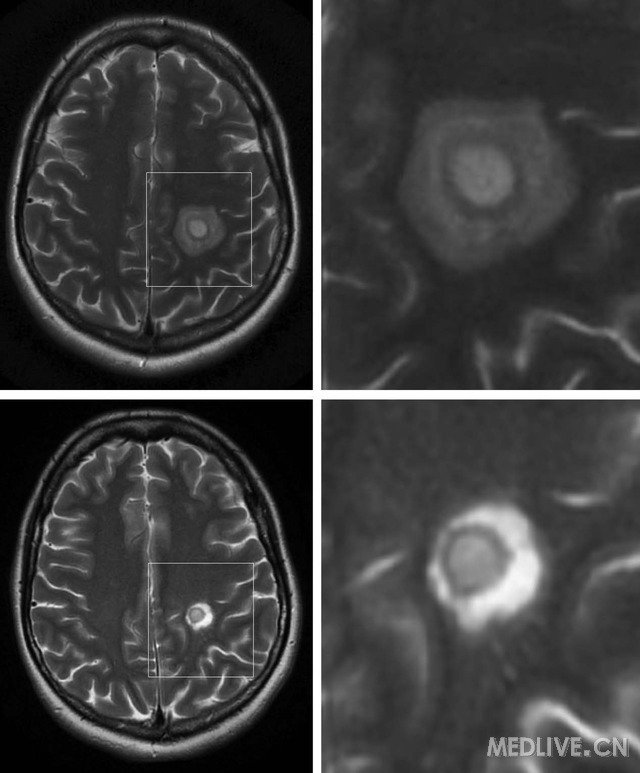

MRI 技术的进展使得 Balo 同心圆硬化能够在患者活着的时候就进行诊断。T1 加权成像显示 Balo 病变典型表现为交替等信号和低信号的同心圆样病灶;T2 加权序列显示在所谓的 T2 高信号的风暴中心周围环绕着高信号的片层样结构;尽管也可见其他复杂的结构描述,包括马赛克式,莲花座状,或康乃馨状,甚至双杠状 ( 见图 1)

1. MRI 显示左侧顶叶同心圆硬化病灶。A 图为 T1 加权像,B 图为 T2 加权像。

Balo 或 Balo 样病灶的结构因一个或两个至几个交替的脱髓鞘条带不同而不同,其病变大小可以小至不足 1厘米,也可以大到累及整个大脑半球 ( 图 23)Balo 病变可能是多个病灶起病或孤立性病灶。连续的 MRI使得能够对新形成的 Balo 病灶的演变有深入的认识,尽管研究对于洋葱环状结构是同时出现还是从核心遵循一定的半径向外发展尚有争议。

2. MRI 显示在采用皮质激素治疗前后左侧顶叶同心圆硬化病灶。A 和 B 图(3 倍放大)为 T2 加权像,C图和 D 图(4 倍放大)为采用静脉甲基强的松龙治疗 2 个月后的 T2 像。